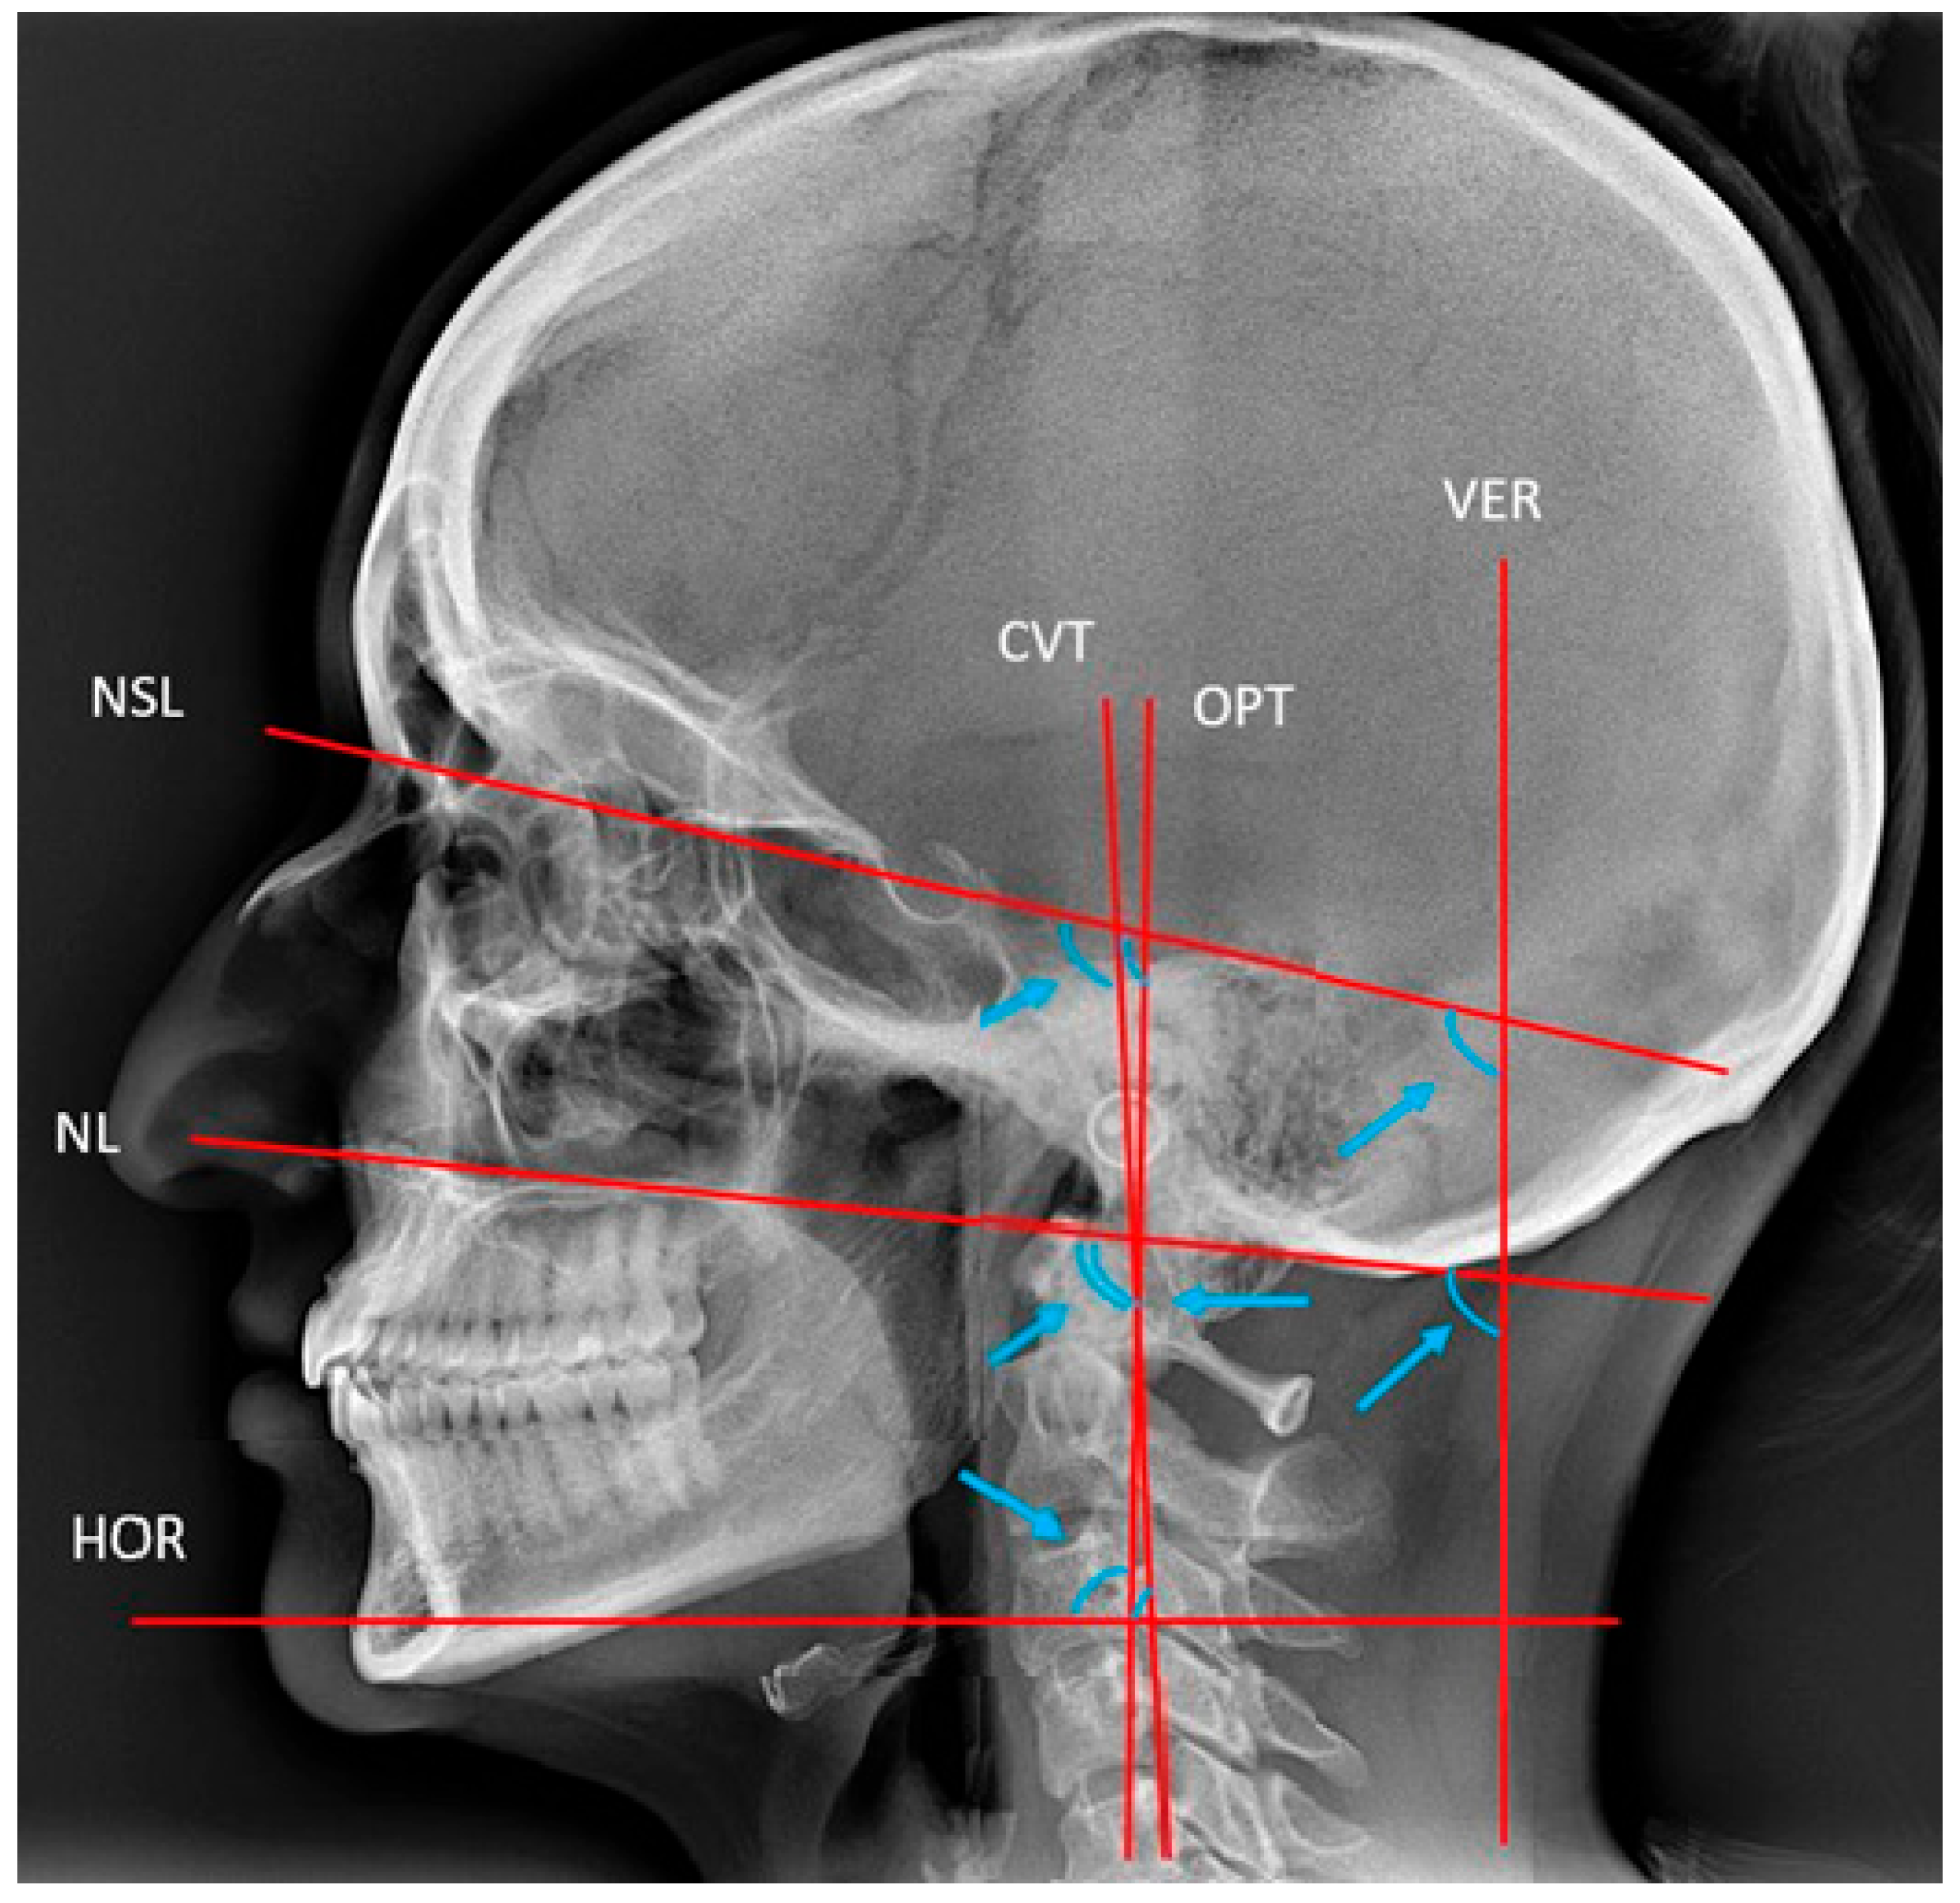

Head posture was measured as described by Solow and Tallgren [24], and reference points and lines are described in Table 3 and illustrated in Figure 5 [24].

Figure 5.

Reference lines and angles used for the description of head posture [19]. VER and HOR, true vertical and horizontal lines. CVT and OPT, cervical and odontoid process tangents. NL and NSL, nasal and nasion–sella lines. The arrow heads point to the angles NSL/VER, NSL/CVT, NSL/OPT, NL/CVT, NL/OPT, NL/VER, CVT/HOR, OPT/HOR, and the cervical curvature CVT/OPT.